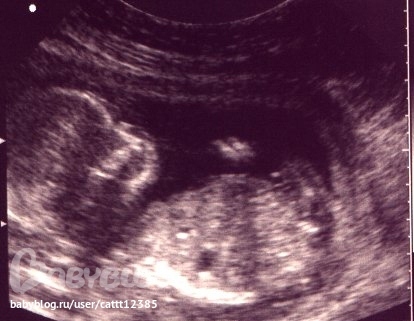

А сегодня мы уже большие и нам 22 недели!!! Вчера были на узи, нам все померили и сказали ВСЕ У ВАС ХОРОШО, ВСЕ ПО СРОКАМ!!! Увидели НАШУ МАЛЫШКУ!!! Столько раз делали узи и ни разу она нам не показывала себя, а вчера все таки, после получасового скольжения датчика узи по моему животику все-так и рассмотрели. Хорошо узистка попалась терпеливая и очереди после нас не было. Мы вовсю пинаемся, шевелимся и радуем бабулечек!

А сейчас мы, примерно, такие (как на этой картинке из интерета):